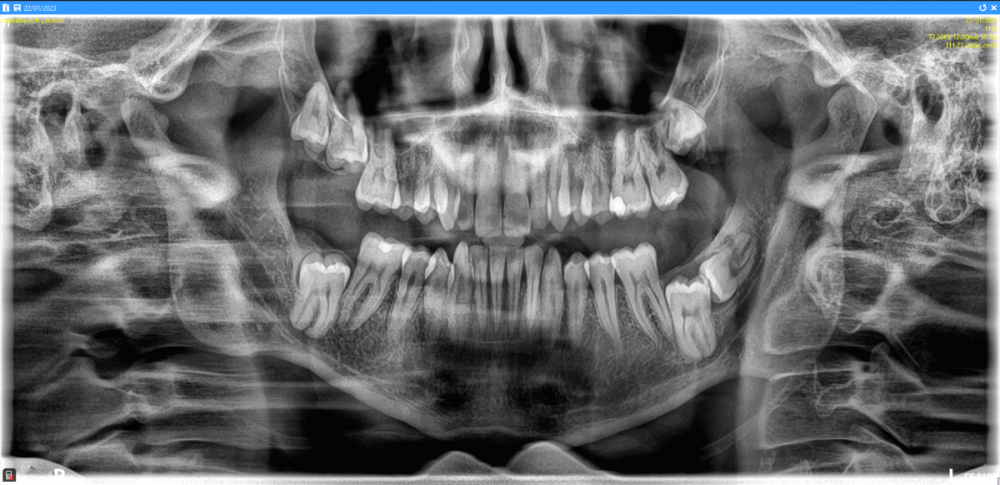

msp Опубликовано 22 января, 2023 Автор Поделиться Опубликовано 22 января, 2023 (изменено) Всем привет, Сделал панорамный снимок. Что можете сказать - какие из этих ретинированных зубов можно "вырастить"? Заранее спасибо Изменено 22 января, 2023 пользователем msp Ссылка на комментарий

red_butler Опубликовано 23 января, 2023 Поделиться Опубликовано 23 января, 2023 крайне мало вероятно что восьмые и седьмые зубы прорежутся. Требуется консультация ортодонта и Кт 2 Ссылка на комментарий

msp Опубликовано 23 января, 2023 Автор Поделиться Опубликовано 23 января, 2023 3 часа назад, red_butler сказал: крайне мало вероятно что восьмые и седьмые зубы прорежутся. Требуется консультация ортодонта и Кт А от чего зависит вероятность их прорезывания? Так-то у меня все зубы в отличном состоянии, пломб минимум и только поверхностные. Ссылка на комментарий

msp Опубликовано 23 января, 2023 Автор Поделиться Опубликовано 23 января, 2023 Может быть можно их "вытянуть"? Ссылка на комментарий

АнтонТЛТ Опубликовано 23 января, 2023 Поделиться Опубликовано 23 января, 2023 4 часа назад, msp сказал: Может быть можно их "вытянуть"? Может быть можно, нужно смотреть КЛКТ Ссылка на комментарий

red_butler Опубликовано 24 января, 2023 Поделиться Опубликовано 24 января, 2023 12 часов назад, msp сказал: А от чего зависит вероятность их прорезывания? факторов очень много, например наличие места в челюсти и отсутствие анкилоза зубов. 12 часов назад, msp сказал: Может быть можно их "вытянуть"? 15 часов назад, red_butler сказал: Требуется консультация ортодонта и Кт 1 Ссылка на комментарий